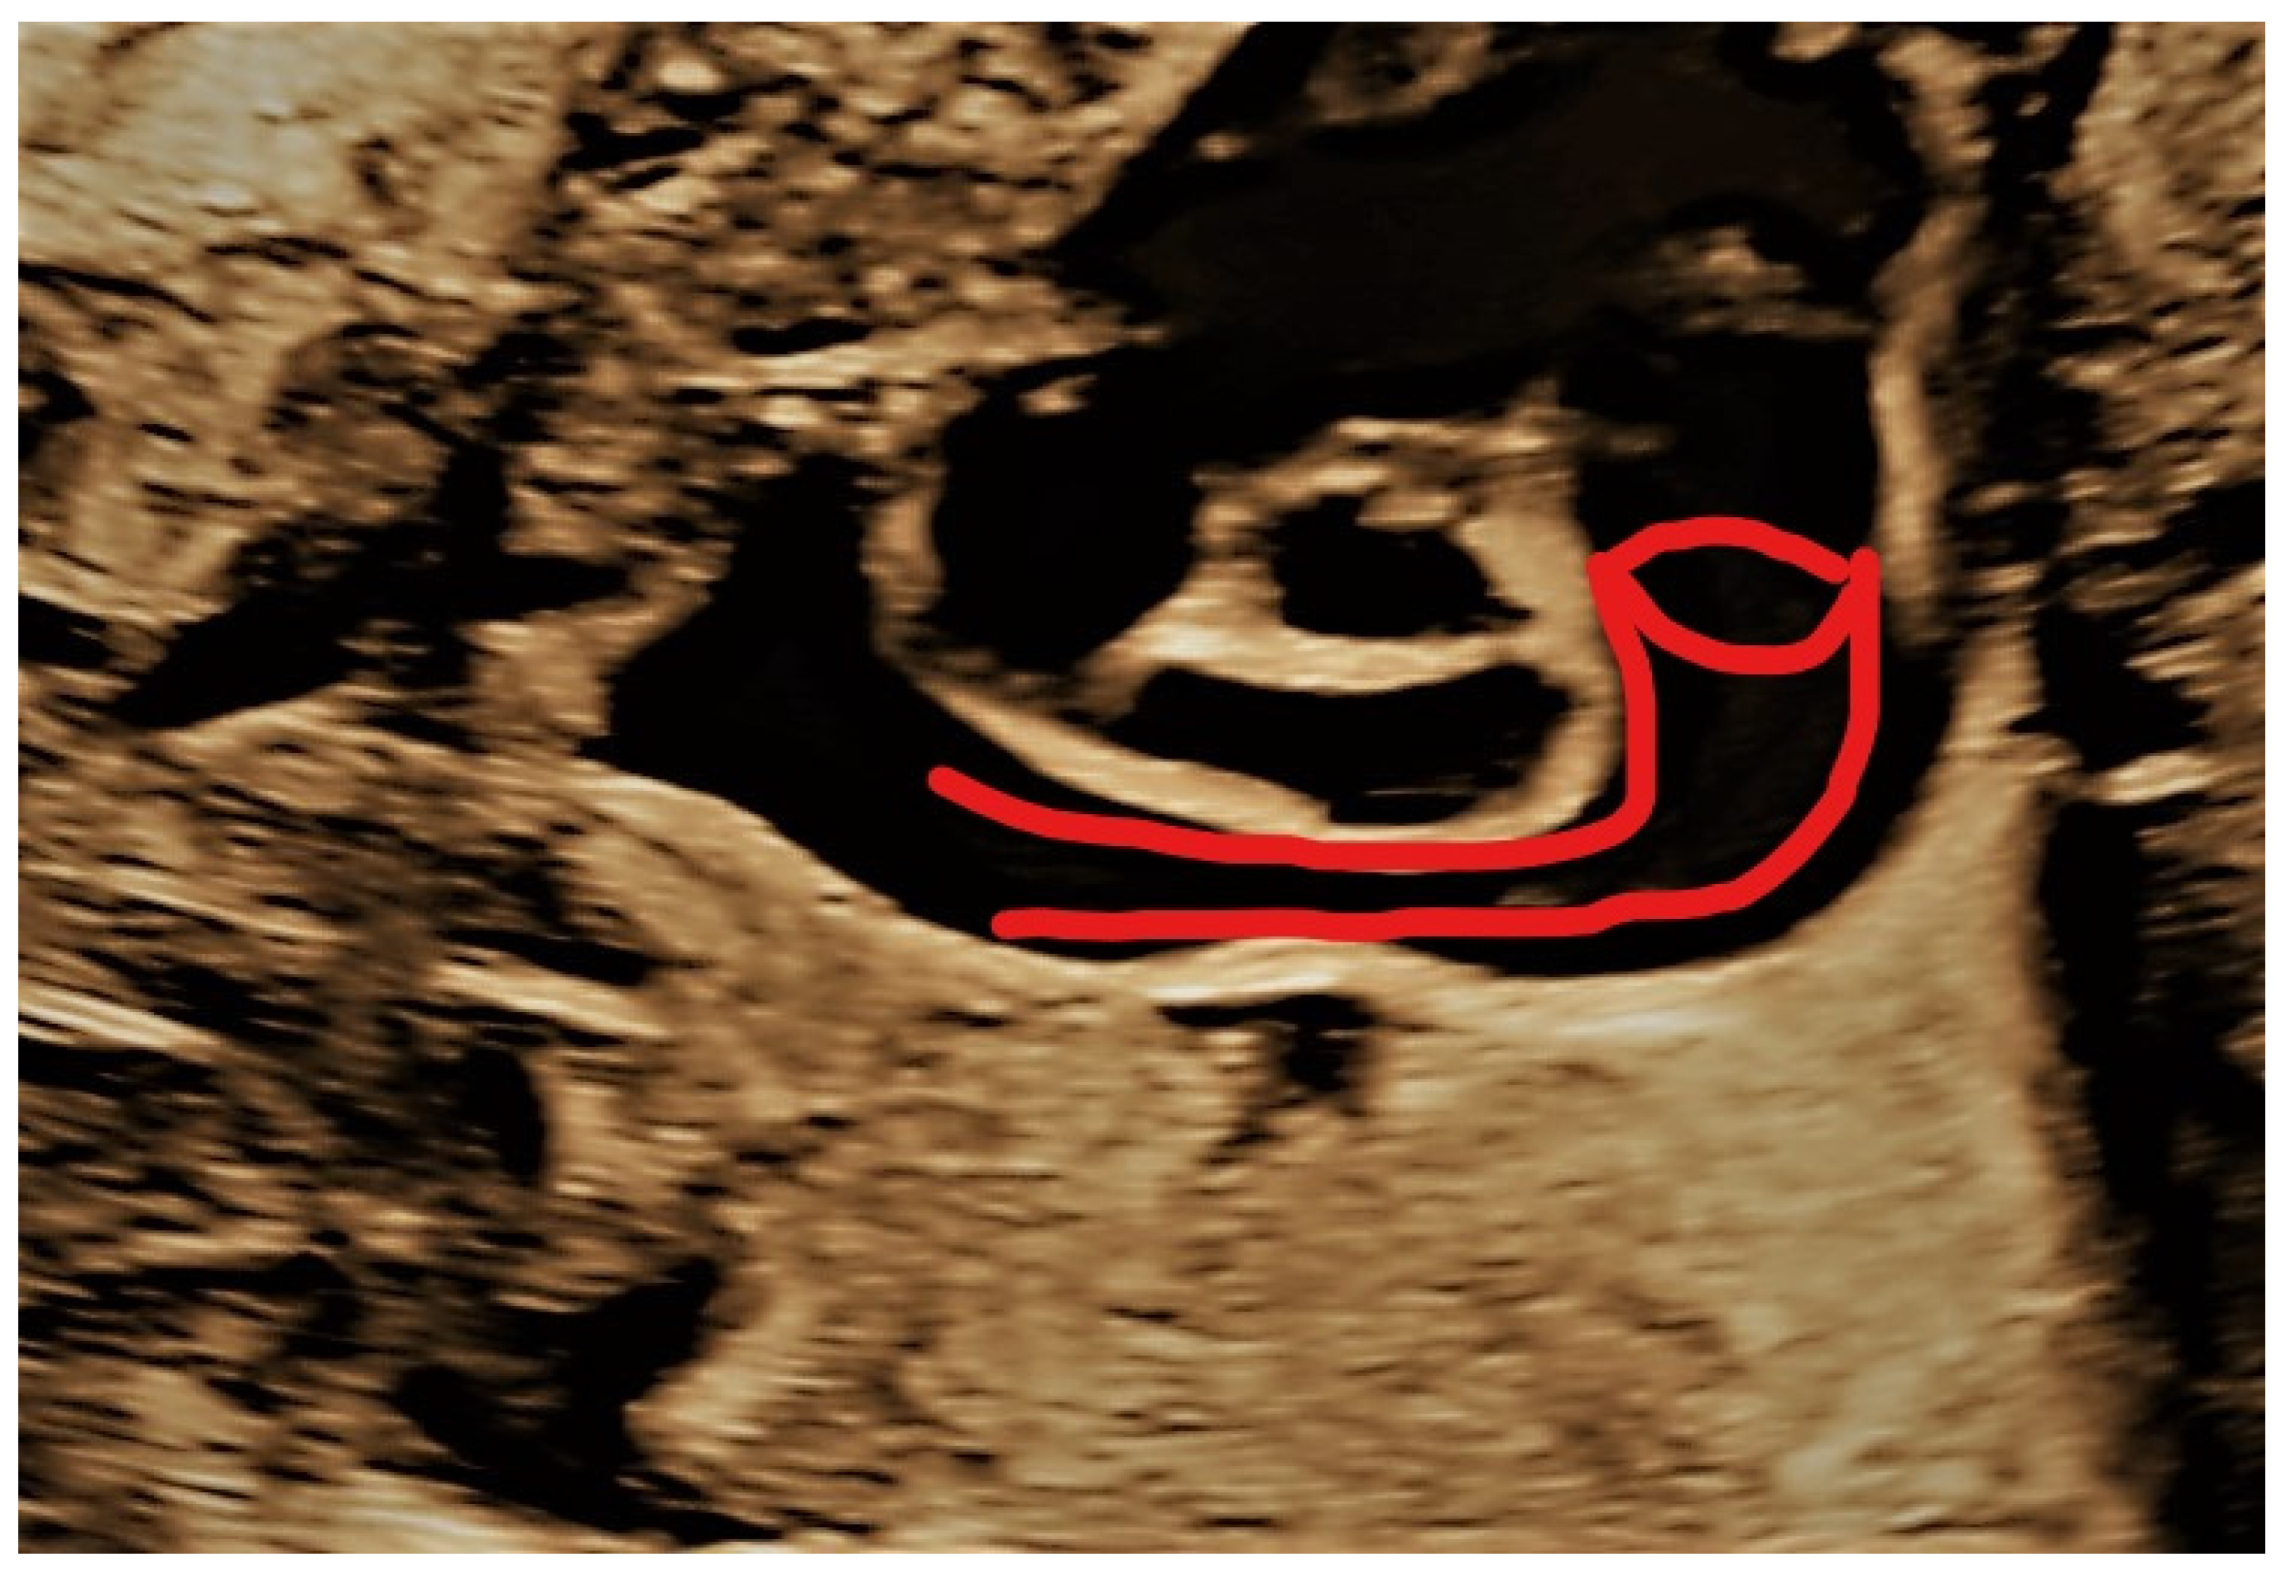

4.3. Case 3